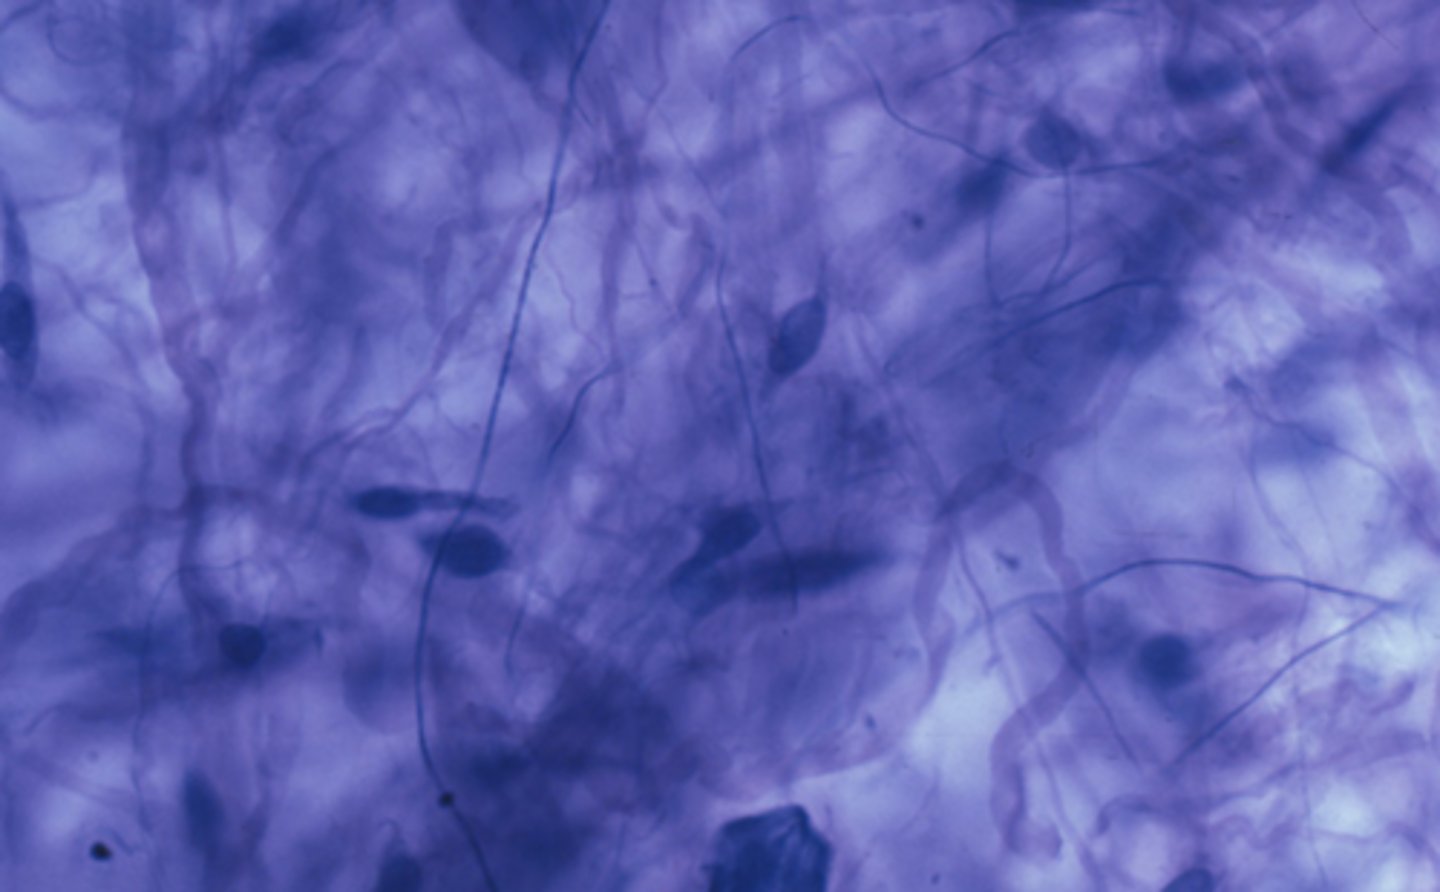

connective tissue

Which of the four major tissue types is presented in the following image of the mesentery? (Hint: just answer one of the four major tissue types here, we don't need subtypes)

Cells produce an extracellular matrix

Which is a characteristic of the tissue type in the previous image: Connective Tissue